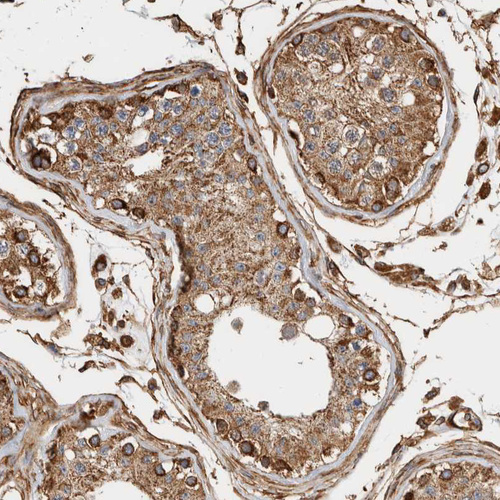

Immunohistochemical staining of human testis shows strong granular cytoplasmic positivity in cells in seminiferous ducts.